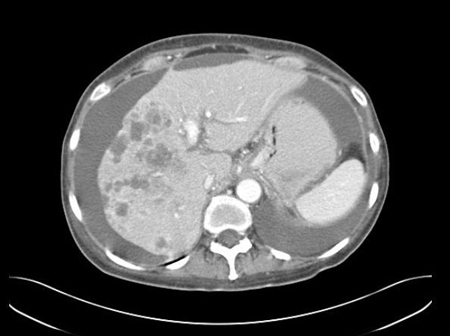

TC abdominal com contraste intravenoso, revelando diversas lesões com realce no lobo hepático direito, com ascite associada; a biópsia percutânea de uma dessas lesões revelou adenocarcinoma, mas nenhum sítio primário foi identificado durante a investigação de rotina: uma manifestação típica de ASPD

Do acervo pessoal do Dr. D. Cosgrove